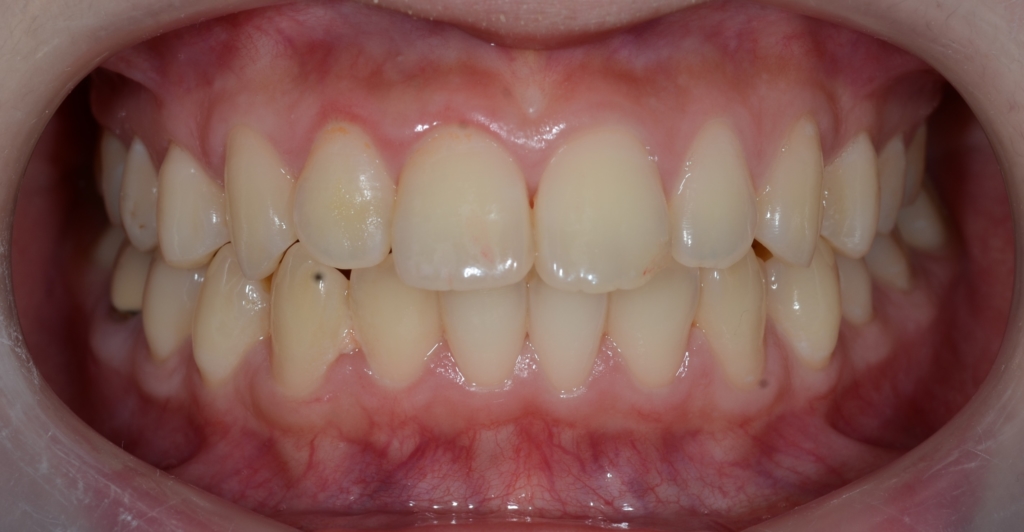

ついでに、歯並びの比較です

上段が矯正治療前、下段が矯正治療後